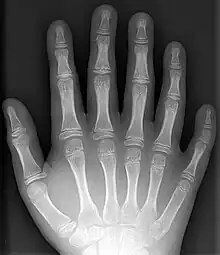

- Polydactyly – additional fingers or toes[4]